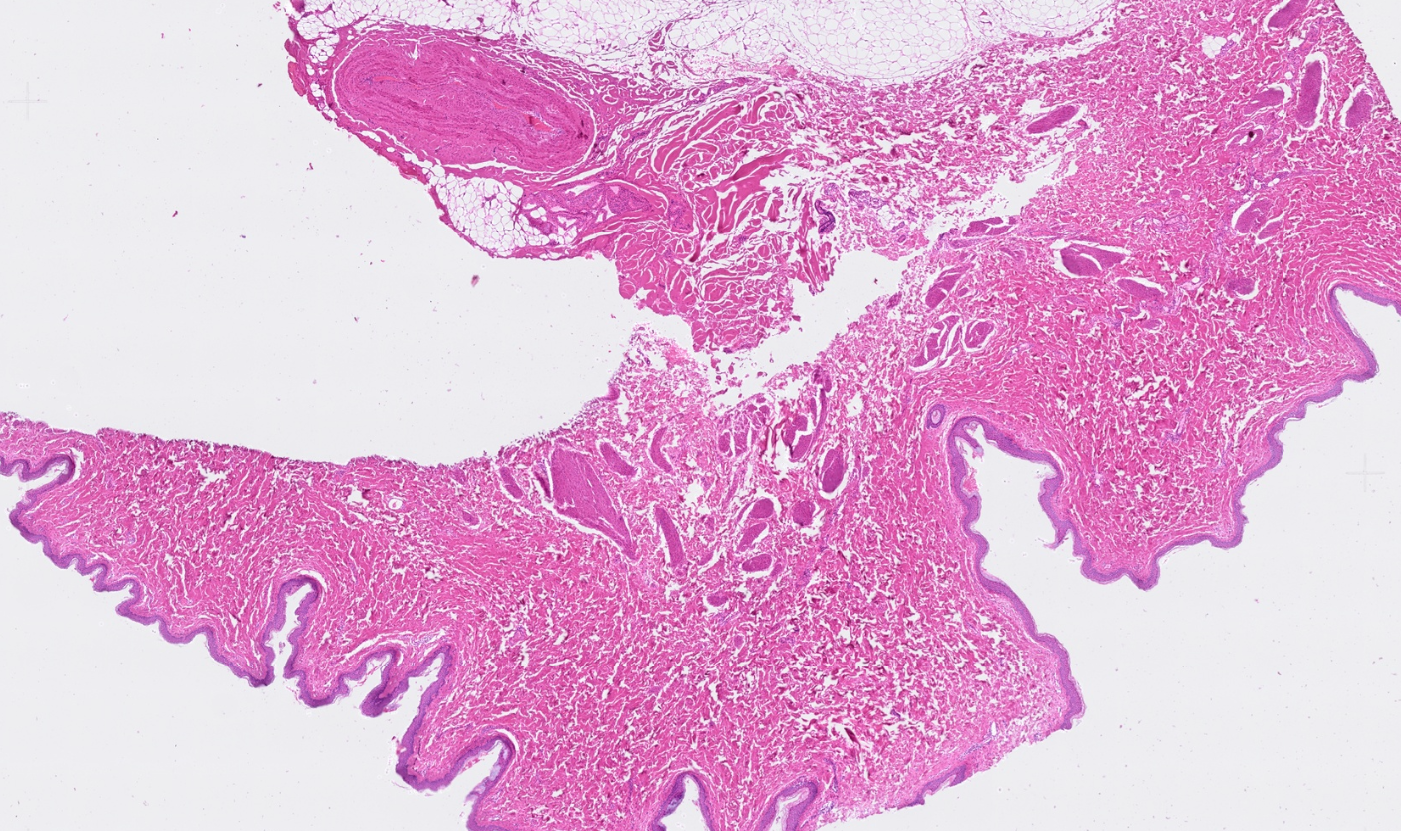

The segmentation module is designed to generalize across a wide range of biological tissues. Below are representative benchmark results based on 10x Genomics demo datasets:

Brain

Pancreas

Colon

Liver

Ovary

Kidney

Lung

Skin

Lymph node

Applicability across different spatial resolutions

The segmentation module is designed to help researchers explore tissue architecture at multiple levels of detail, depending on their scientific question. Users can begin by dividing the tissue into major anatomical structures to gain a broad overview of the spatial landscape. From there, they can zoom into a specific region of interest and further segment it into sub-tissue compartments, enabling more refined analysis of microenvironments and localized biological processes.